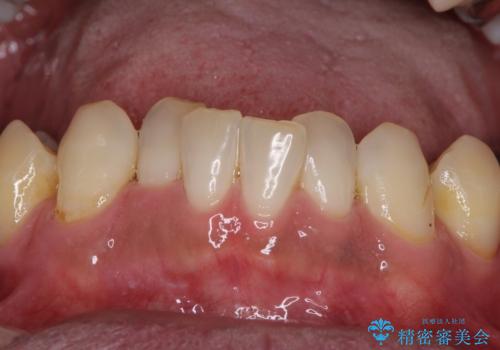

- 前歯がのデコボコや、奥歯に咬んだときに痛みがあるとのことで来院された患者様です。

全体的に問題が多く、全てをしっかりと治療したいとのことでした。

全体的に中等度の歯周病と診断されたため、歯周外科処置やインプラントによる咬合回復から進めて行き、矯正治療による歯列改善を行った後にオールセラミッククラウンにて補綴することとしました。

歯槽骨の再生治療を行ったため、外科処置後の静置期間がながくなり、4年弱の治療期間となりました。